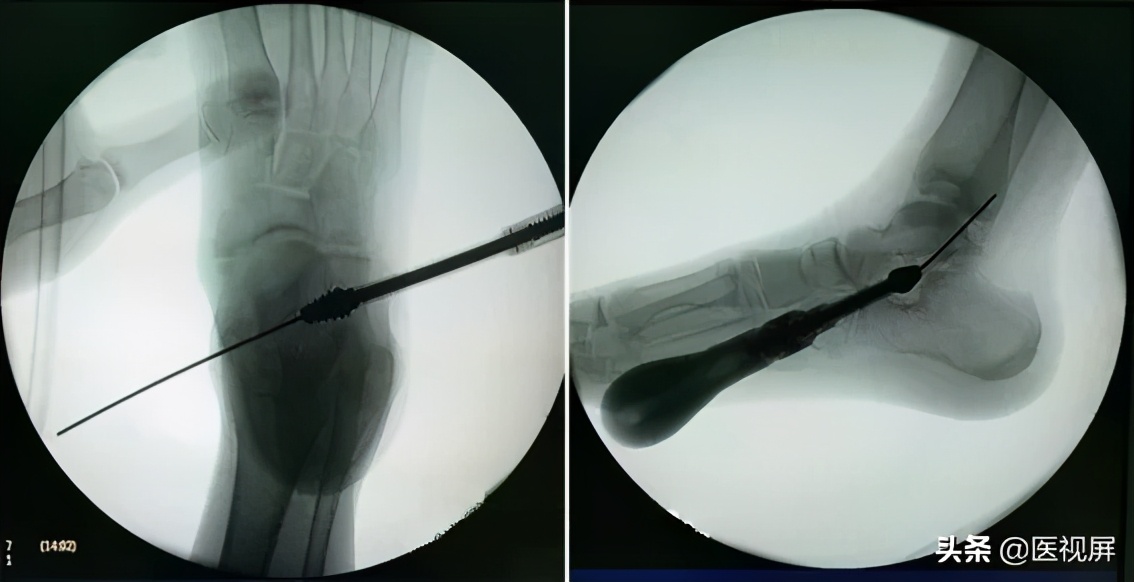

自外向内置入钝头导针(图5),通过跗骨窦至内侧皮下。于内侧做经皮划开皮肤,导针穿出。导针位于胫后肌腱上方,胫前肌腱内下方,内踝下。置入试模时,将足置于内翻位,制动器在前后位X线上尾部距离跟骨外侧缘1cm,并且头部不超过距骨中轴线(图5)。选择合适大小的试模。

▲图5 打入导针并置入试模